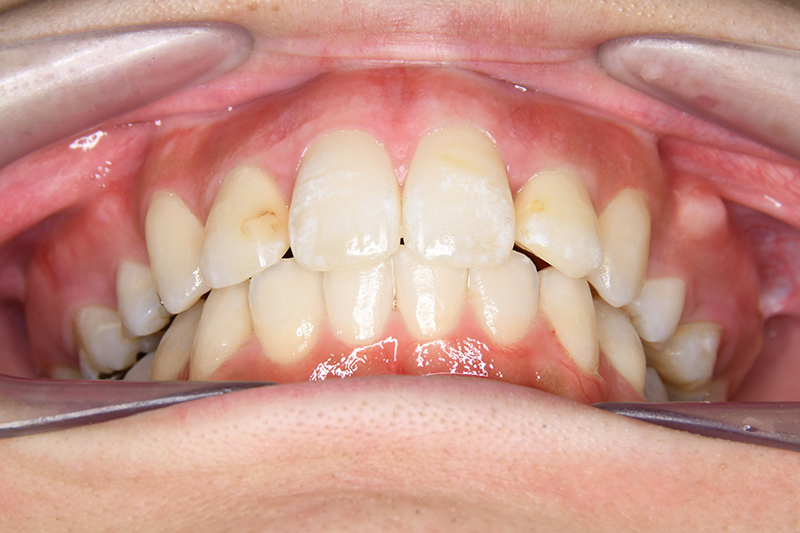

初診時

FP・IOP

顔貌所見 正貌はほぼ対象。側貌はconvex type、著しい口唇閉鎖不全が認められた。

口腔内所見 over jet 11.5mm、over bite 5.5mm、右側臼歯関係Full ClassⅡ級、左側end onⅡ級、上顎顎歯列はテーパー型であり、上顎中切歯は押し出されるように大きく唇側傾斜していた。下顎前歯部は叢生を呈しており、左下5は歯冠長が短く半埋伏していた。